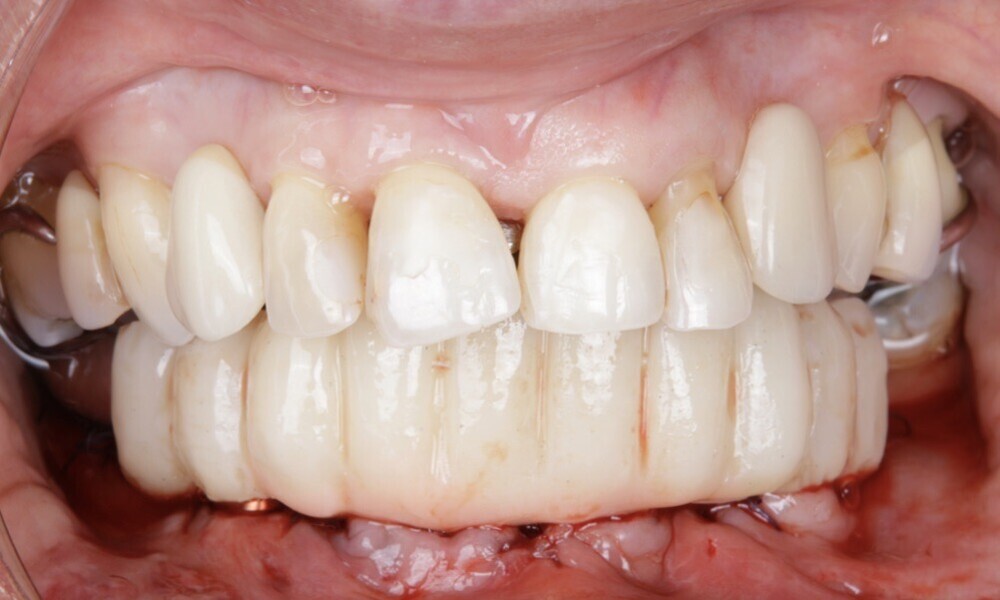

The soft tissue was in good condition, and the definitive restorations were placed (Figs. 76 & 77). After placing the definitive restorations, oral hygiene instructions were given to ensure proper care and prevent complications. Additionally, the occlusion was carefully checked and adjusted as needed (Figs. 78–83).

Figs. 78–82: The definitive restorations were placed, and occlusal adjustments were performed.